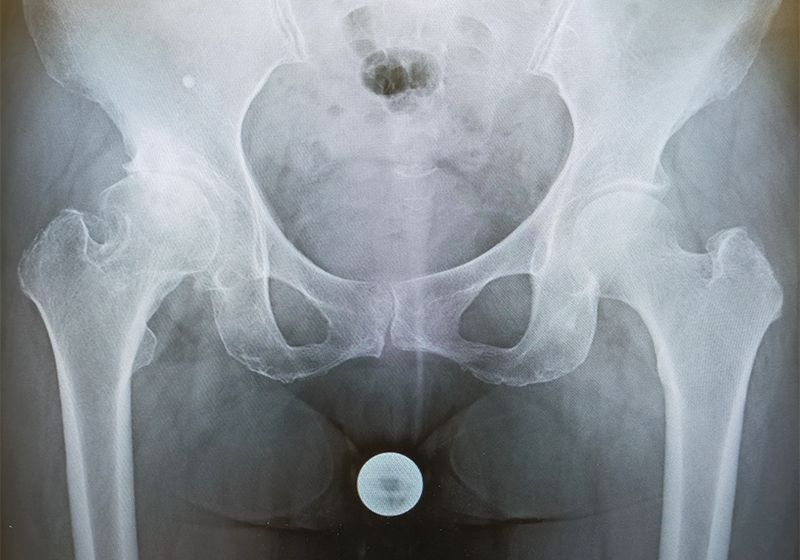

両側とも股関節は上外側に脱臼し、腸骨部に新たな関節が形成されています(二次臼蓋)。股関節の変形に伴い、関節の動きも大きく制限されており、左膝の関節症(X脚変形)も生じていました。左右の脚の長さに差が生じるために、骨盤は傾き、背骨も変形しています。

脊椎・骨盤〜股関節〜膝はそれぞれが連動して機能しており、単一の障害ではありません。全体のバランスを考えて治療法を考える必要があります。

このように変形が高度な症例では、通常の人工股関節での治療は難しく、特殊な人工股関節置換術が必要となります。

今回の症例では、まず左股関節症に対して大腿骨短縮骨切り併用THAを行いました。

正確な人工関節の設置が非常に難しいため、3Dテンプレートによる綿密な術前計画と、患者様ご本人の実物大の3D骨モデルを作成し、手術を行いました。